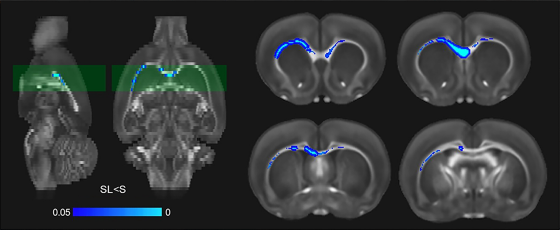

次にラットを用いた実験では、睡眠を10日間制限した後に白質の指標が低下し、電子顕微鏡で髄鞘が薄くなっている様子が確認されました。研究チームは、軸索そのものの太さは大きく変わらない一方で髄鞘側の変化が目立った点がポイントだとしています。